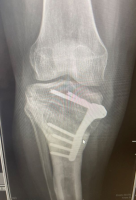

Mr Mughal is also highly experienced in deformity correction for both adolescents and adults, including knock knee, bow leg deformities and the complex condition known as miserable malalignment syndrome. He uses advanced computer based and 3D modelling techniques to plan personalised corrective surgery, aiming to preserve joints affected by early osteoarthritis. When combined with cartilage regeneration procedures, this approach enables him to offer a comprehensive and tailored treatment pathway.

Tibial osteotomy - (5-50)

Open surgical stabilisation of patella, including soft tissue/tendon transfer or release, +/- application of cast (adult) - (1-5)